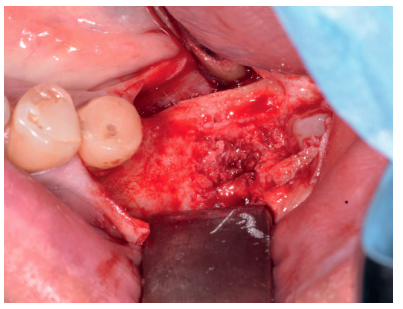

Al quinto mes se realizó un CBCT de control, para evaluar la homogeneidad en la zona y se planificó la colocación de un implante corto de 5 x 6 mm de Proclinic® (Figura 9) al mismo tiempo que fue tomada una biopsia de la zona. Se procedió a inyectar la misma anestesia que en la primera cirugía, se elevó un colgajo a espesor total y se tomó una biopsia con trefina de 3.5 mm de la zona injertada (Figura 10). En la misma zona donde fue realizada la toma de biopsia, sin pasar ninguna otra fresa, se colocó el implante empleándolo como expansor, de modo que se condensasen las paredes que rodeaban al implante (Figura 11).